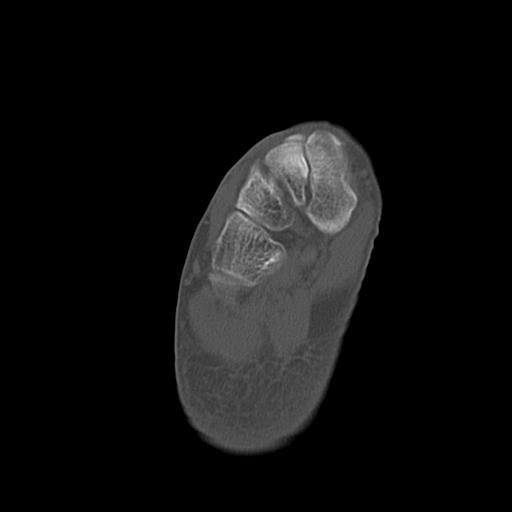

102755 1/4 2R 1/15 2R 右足関節 68歳女性 右三果脱臼骨折